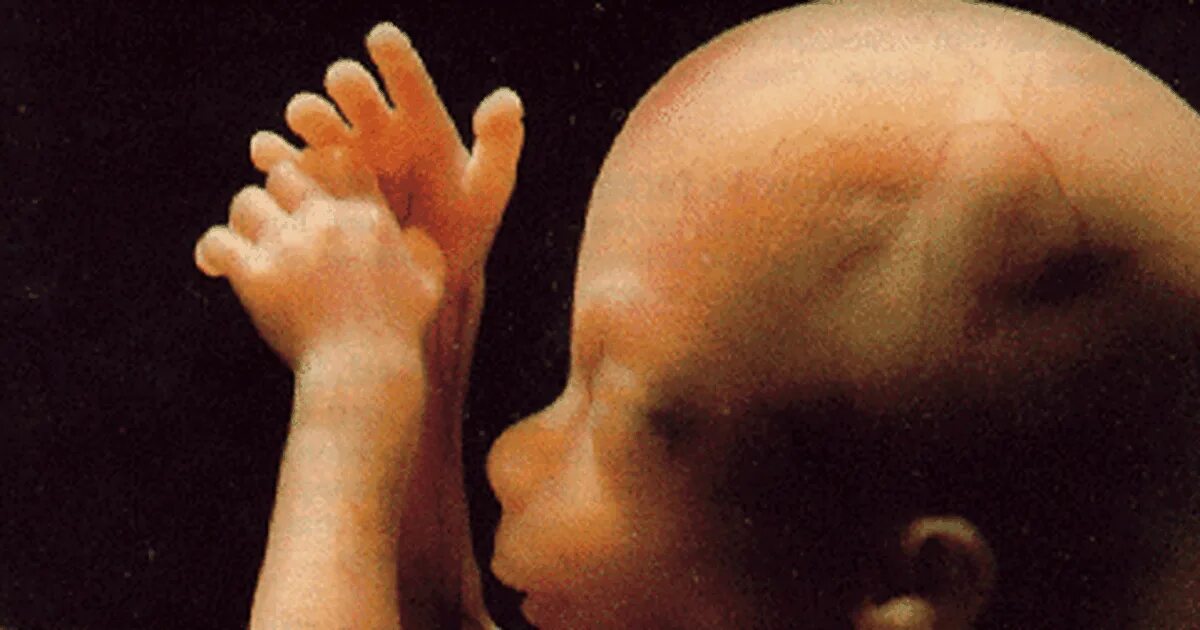

Беременность беременна 18 недель